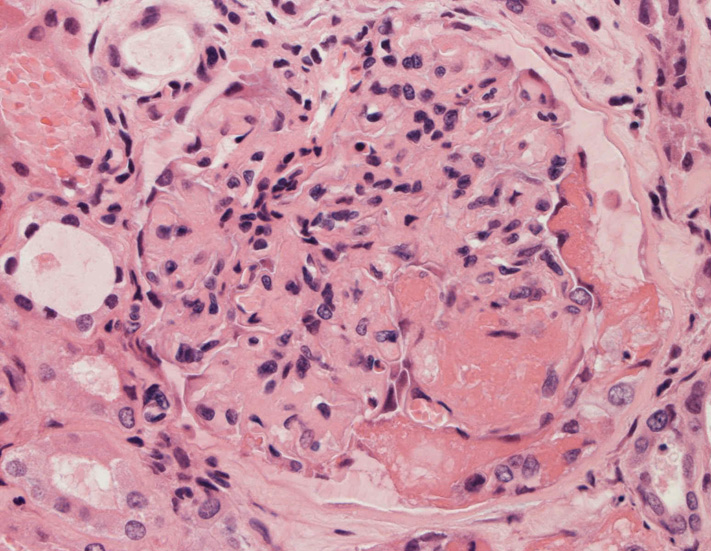

腎臓の病理組織所見-->壊死性糸球体腎炎

kidney01.jpg

kidney02.jpg

Fig.01Fig.02Fig.03